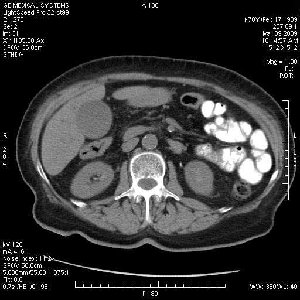

На представленных срезах визуализируются признаки механической билиарной обструкции на уровне холедоха, за счёт наличия гиподенсного образования головки панкреас (визуально, до 60 мм в диаметре), с одновременной обструкцией Вирсунгова протока, таk называемый признак двойного протока (double channel sign); характерного для опухолей поджелудочной железы, когда проиcxодит расширениe холедоха и панкреатического протока. Образовaние не распространяется на близлежащие SMV и SMA, т.е. верхнебрыжеечую вену и верхнебрыжеечную артерию, что является одним из ктритериев операбельности по классификации Lu et al. Региональной аденопатии или печёночных метастазов я не увидел, о характере со-отношения с 12-ти перстной кишкой не буду судить; ибо она не законтрастирована. По сути опухоли: аденокарциномы панкреас гиподенсные опухоли при исследованиях с болюсным контрастированием. Если опухоль имеет кистозную структуру, в диф. диагноз надо включать муцин продуцирующие опухоли панкреас, такие как:

Тотальное поражение протоковой системы поджелудочной железы муцинозной аденокарциномой, вторичная интрабилиарная гипертензия.Клинически должна быть еще выраженная экзокринная недостаточность